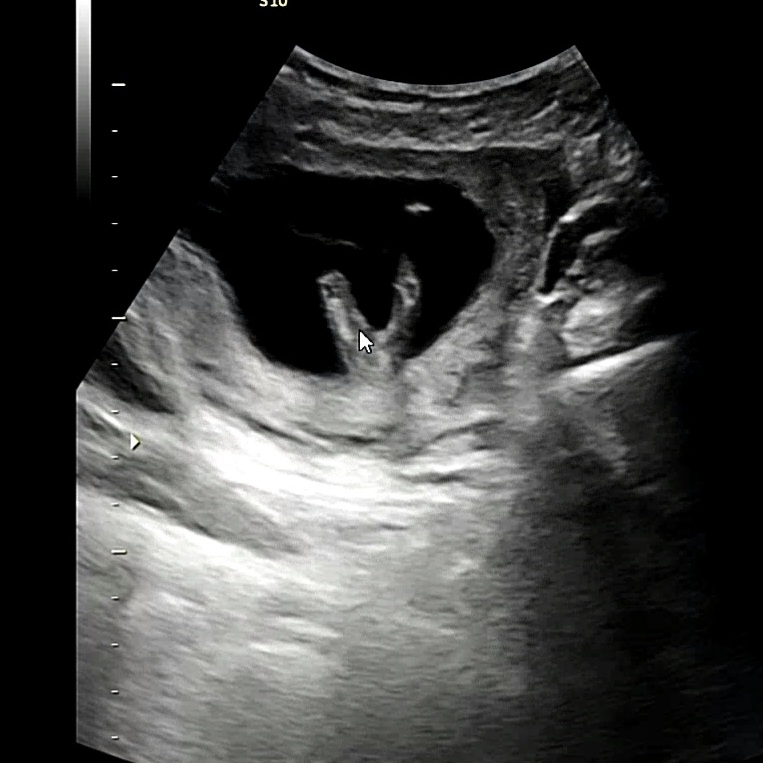

초음파 사진으로 성별 봐주세요

선생님이 딸로봐주시긴 했는데 13주라 정확하지않아서.. 바뀔수도있나요?